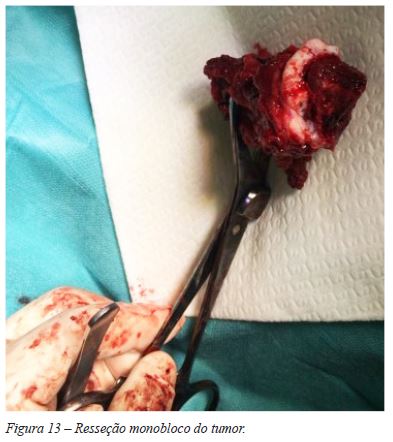

Introduziu-se a lâmina de bisturi na fise, de forma a separar a epífise e metáfise umerais proximais, conseguindo-se uma ressecção monobloco, sem visualização macroscópica do tumor (Figura 13). Colheram-se amostras de tecido ósseo do topo distal do úmero e da zona fisária residual na epífise umeral, tendo-se enviado o material para estudo anatomo-patológico e confirmação das margens de ressecção. De seguida, foi realizada a preparação de enxerto alógeno de úmero - com confecção de corte para encastoar no úmero nativo distalmente e para melhor adaptação a nível epífise. Fixou-se com lâmina-placa 90º, mantendo o cravo proximal para orientação da mesma (Figura 14). A fixação foi reforçada com a aplicação de uma placa recta LCP 3,5mm num plano ortogonal relativamente à outra placa (Figura 15). Ambas as placas foram aplicadas em compressão. Não se registaram intercorrências peri-operatórias.